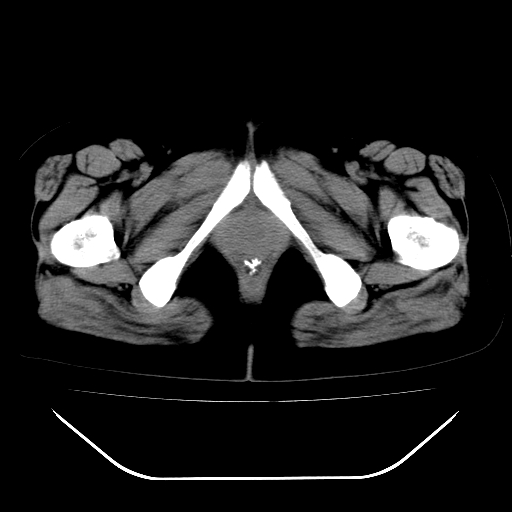

标题: CT28584:女,48岁,肛门坠胀感一年,肠镜未见异常。 [打印本页]

女,48岁,肛门坠胀感一年,肠镜未见异常。

子宫明显增大,形态不规则。多考虑:子宫肌瘤!

子宫明显增大,形态不规则,  盆腔积液 结合临床考虑:1子宫肌瘤, 2  盆腔炎。

道格拉斯窝积液考虑慢性盆腔炎,宫腔少量积液,子宫肌瘤不好说,建议增强。